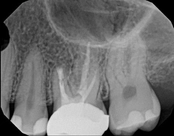

Upper molar failed root canal and apicoectomy:

Before

Immediately after

3-month follow-upThis person presented with one root that had failed from root canal treatment. The arrow in the picture, shows the infection as well as extra filling material that was pushed out of the root. An apical microsurgery was performed using the laser. The infection and excess material was cleaned out. Complete healing is visible 3 months after. The tooth was saved. This is a poor area for an implant.